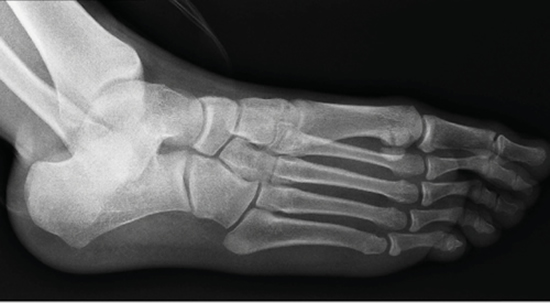

The ossification process of the human being follows a sequence of identifiable physiological events in the bone structure of the skeleton, both in the direct morphological examination, and in the observation of these through radiography (Figure 1). In clinical practice, it is important to accurately know the bone age of growing individuals in order to assess their state of development and thus establish a correspondence with the chronological age of the subject3.

Figure 1. Oblique X-ray showing the bones of the foot.